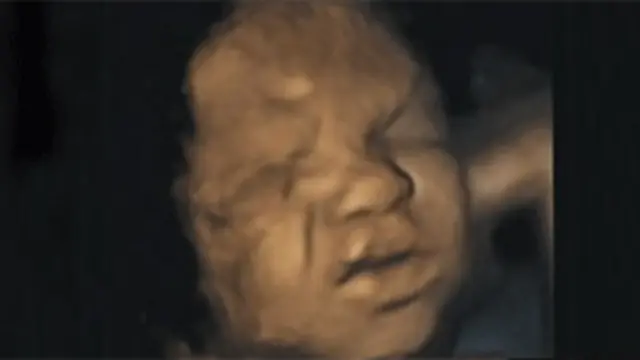

’بچے رحمِ مادر میں بھی روتے ہیں‘

برطانیہ کی ڈرہم اور لنکاسٹر یونیورسٹی کی تحقیق کے مطابق رحمِ مادر میں موجود بچے اپنے چہروں پر درد کے تاثرات لانے کی مشق کرتے ہیں۔

الٹراساؤنڈ سکین کے مطالعے سے اندازہ ہوتا ہے کہ حمل کے دوران جنین مسکرانے ، بھنوؤں کو نیچے کرنے اور ناک چڑھانے جیسی حرکات کرتا ہے۔

اس تحقیق میں آٹھ مادہ اور سات نر جنین کے فور ڈی سکینز کی ویڈیو فوٹیج کا مطالعہ کیا گیا۔